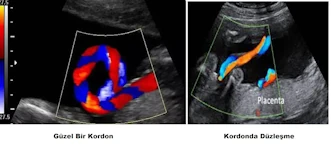

Kordonun helikal yapısı çok önemlidir. Bunu şu şekilde anlatmak iyidir. Elinize 3 tane bildiğiniz hortum alınız, normal bahçe – balkon yıkanır iken kullandığımız hortumlardan; bunlar tek halde iken üzerlerine baskı uygulandığında büzüşürler, baskıya karşı mukavemeti azdır.

Eğer 3 hortumu birbiri üzerine sık şekilde sarmal yaparsanız, hortumların basıyla kapanması (mesela oligohidramnios, yetersiz rahim hacmi, gibi sebepler …) güçleşecektir. Bebeğe kan akışının kesintisiz, sürekli olabilmesi için kordon sarmalının fazla olması gereklidir. Bu sarmal eğer az ise; kordonda düzleşme oluşmaya başlar, düzleşen kordon, bası altında kapanmaya meyillidir. Düzleşmiş kordonu olan bebek, doğum eylemini kaldıramayabilir, su azalmasını tolere edemeyebilir, kordonda düğüm olduğunda fetusun hipoksi yaşama olasılığı artar, … İşte bunlardan dolayı ayrıntılı ultrasonun tecrübeli klinik jinekolog tarafından yapılması elzemdir.

Kordon Heliks Yapısının Değerlendirilmesi